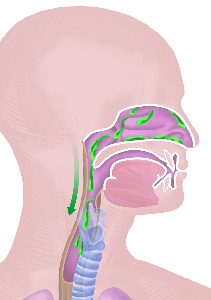

Detailreiche Fotografien aus der medizinischen Praxis ergänzen die Texte; moderne, genaue,

wissenschaftliche Zeichnungen geben Einblick in die Anatomie und die Funktion der Lunge und

anderer Organe.